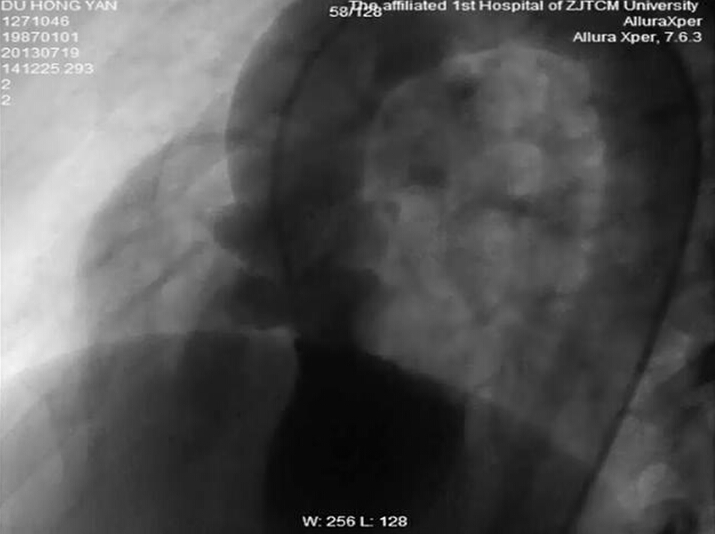

小陈很快被安排手术,在局部麻醉情况下,毛威教授和蔡宏文副主任医师开始实施“补心”手术。毛教授一边和小陈聊天,一边通过娴熟的血管穿刺和导管操作技术,利用外周血管建立了一条动静脉轨道,通过这条轨道将一把折叠的“小伞”缓缓送入心脏,从X线影像上,能够清楚地看到这把“小伞”很快抵达心脏并穿过室间隔的漏洞,随着精细的心内导管操作,折叠的“小伞”慢慢滑出伞柄(输送鞘管)并撑开,随着心脏的跳动,“小伞”精准地与漏洞的两边贴合在一起,重复造影,漏洞被堵住了。毛威教授指着屏幕上的“小伞”说,它叫封堵器,是由可以变形的记忆合金铸造,它暴露在血液里就会自动恢复形状,成为两个圆形伞罩,中间由一根细腰连着,刚好把室间隔缺损口的两边堵住,就好比一把小伞,堵住了小陈心中的缺憾,再过两三个月,心脏里的上皮组织就会慢慢爬满封堵器,封堵器也将与小陈的心脏整整融为一体。

室间隔缺损患者术前造影图:造影剂左向右分流